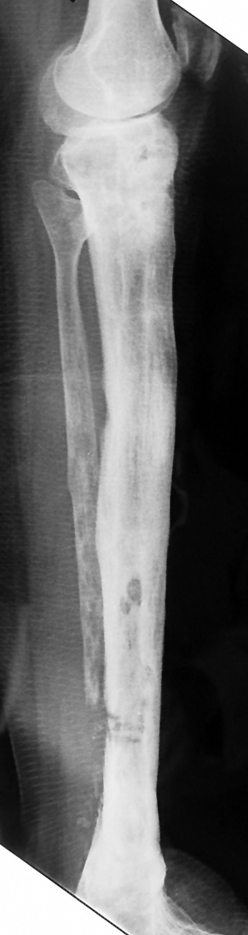

Pseudarthrosis of fracture and pseudarthrosis treatment is currently important problem for orthopedic surgery. Various treatment modalities have been described for pseudarthrosis treatment. All of the treatment methods include high complication rates and additional problems. Leg-length discrepancy, deformity and soft-tissue loss and chronic infection can concomitance with pseudarthrosis. Many internal or external fixation techniques have been described for pseudarthrosis.

Debridement and resection of bone fragment from the pseudarhtosis area vascularized or nonvascularized fibula graft, vascularized muscle flaps, bone grafting followed internal fixation techniques make a option for treatment of pseudarthrosis treatment. But these treatment modalities may not correct deformity and leg-length discrepancy.

Recently, ilizarov techniques which is basis depend on distraction osteogenesis , bone segment transport or acute shortening after the resection at the site of pseudarthrosis combined with lengthening at another level of bone have been used. These treatment techniques may include some advantage for problems of infection, leg-length discrepancy, soft-tissue loss, and joint contracture.